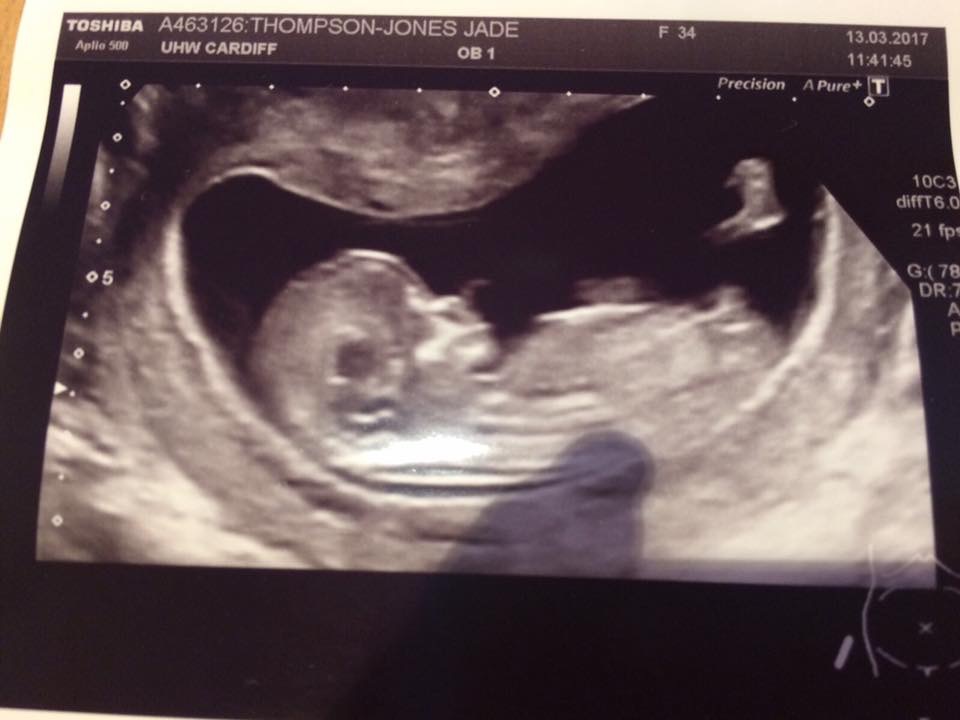

Can you please let me know if you think boy or girl?Attachment 35377Attachment 35379Attachment 35380

I thought the nub looked horizontal to the spine as baby is curved. Was thinking girl but everyone else thinks boy so guess I'm missing something xx

Definite boy, it's all about the stacking!x

Definitely boy! It's the bump above the nub = boy for sure!

The nub is short, angled upward, with stacking above the nub. This is a very classic boy nub. Congrats [emoji170]!